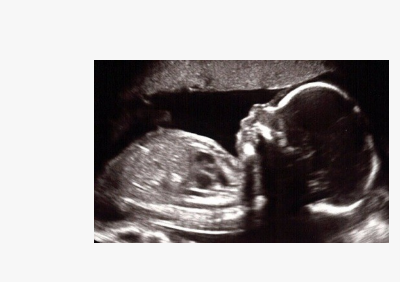

A USG Anomaly Scan is a detailed ultrasound examination performed during pregnancy, usually between 18 and 22 weeks of gestation. It is sometimes called a mid-pregnancy scan or level 2 ultrasound.

The purpose of this scan is to carefully examine the baby’s growth, anatomy, and overall development. It allows doctors to detect structural abnormalities or congenital conditions early and helps plan for the safest care during pregnancy, delivery, and after birth.

A USG anomaly scan is a detailed ultrasound performed during the middle of pregnancy, usually around 20 weeks. It is a screening test that checks for major physical birth defects and helps ensure the baby is developing correctly.

Body parts: Looks at the baby’s developing head, face (for cleft lip), spine, heart, stomach, kidneys, and limbs to ensure they are forming as expected.

Growth and size: Measures the baby’s head, belly, and thigh bone to check if their size is on track for their gestational age.

Placenta and fluid: Checks the position of the placenta and confirms that there is a healthy amount of amniotic fluid around the baby.